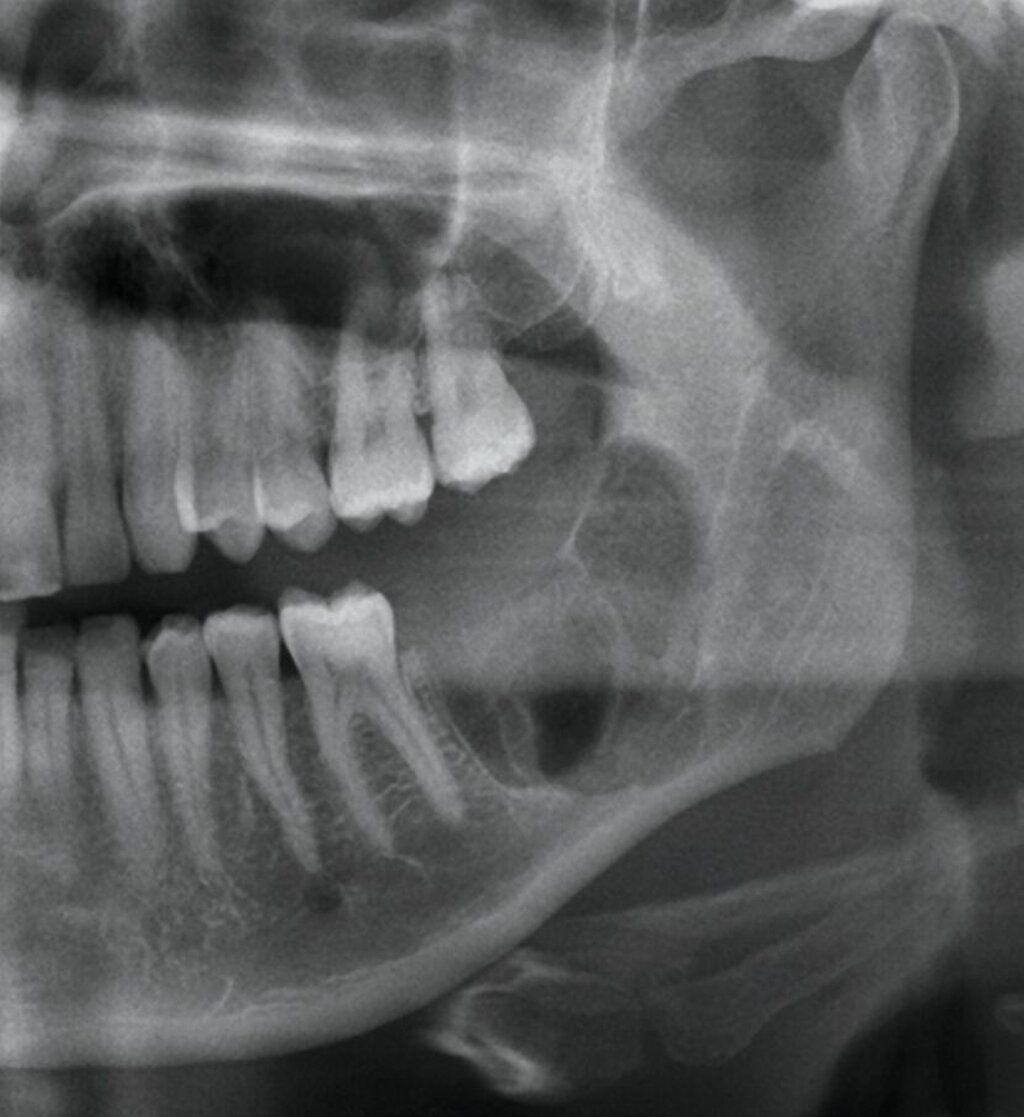

Die seitdem halbjährlich durchgeführten Nachkontrollen zeigen klinisch reizlose Verhältnisse und einen beschwerdefreien Patienten. Radiologisch fand sich eine fortschreitende knöcherne Ausheilung ohne Rezidivhinweise, wie in den Verlaufskontrollen unmittelbar postoperativ, nach einem Jahr und nach zwei Jahren dargestellt (Abbildung 5). Angesichts möglicher Spätrezidive wird die langfristige Nachsorge fortgeführt.